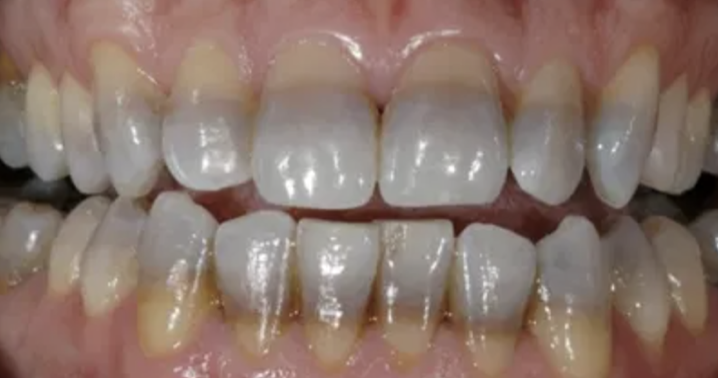

Q

The teeth in the following image are stained due to:

A

tetracycline